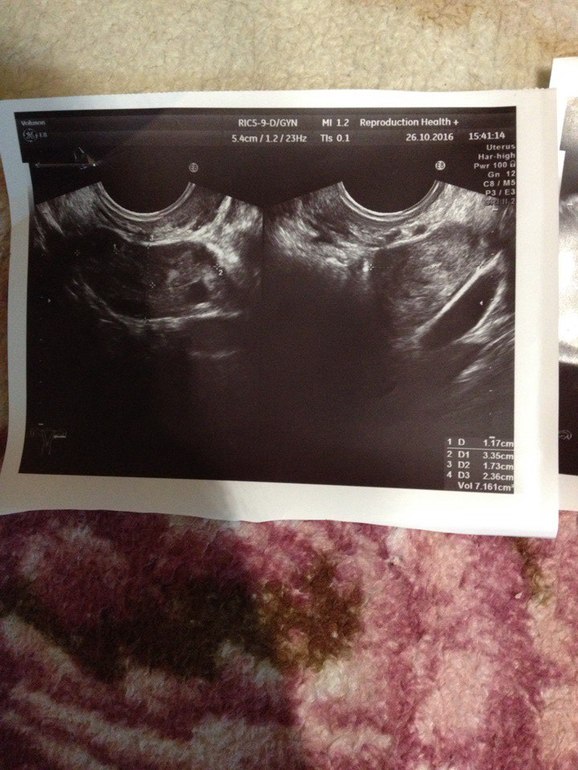

Девочки,может,кто понимает в узи?

Узистка сказала ничего нет в матке..Да и толком вообще ничего не говорила..я спросила: а внематочной есть риск? в ответ: Я не знаю. Через месяц приходите-посмотрим...Я в тихом ужасе..Не знаю что делать..22 ДЗ..

Лада, к сожалению на представленом узи-фото действительно не видно плодного яйца. Но вы не паникуйте раньше времени, может еще появится.